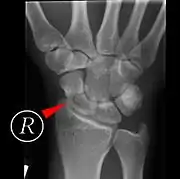

Fractures of the scaphoid are the most common of the carpal bone injuries, because of its connections with the two rows of carpal bones.[1]: 177

Scaphoid fractures may be difficult to diagnose via plain x-ray. A repeat x-ray may be required at a later date, as might cross-sectional imaging via MRI or CT scan.[5]